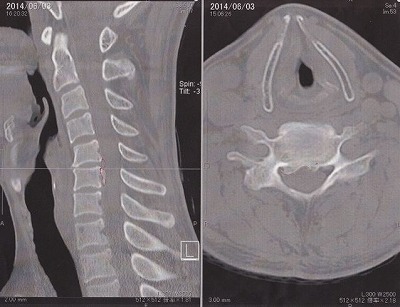

今回、10代の時の怪我が原因で押しつぶされて飛び出した椎間板ヘルニア完全におさらばできました!

2,3年前に一度、右腕の力が入らなくなってしまい頸椎症性神経根症と診断され後方からの除圧術を受けました。

その病院に行くと頸椎症性脊髄症と診断されこのまま放っておくと歩けなく可能性もあると伝えられたのでオペを決心しました。